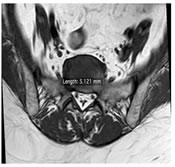

CASE 6

T1W AXIAL IMAGE AT THE LEVEL OF L5-S1 INTERVERTEBRAL DISC SHOWING NARROWED THECAL SAC WITH TRIRADIATE CONFIGURATION AND PROMINENT EPIDURAL FAT WITH MAXIMUM THICKNESS ABOUT 5.12 mm. LATERAL RECESS APPEARS NORMAL

T1W AND STIR SAGITTAL IMAGES SHOWING PROMINENT PERIDURAL FAT AT L5-S1 LEVEL EXTENDING INTO SACRAL CANAL WHICH IS APPEARING HYPERINTENSE ON T1W AND SUPPRESSED ON STIR IMAGE SUGGESTIVE OF EPIDURAL LIPOMATOSIS. IT IS CASUING SIGNIFICANT NARROWING OF THECAL SAC AND ASSOICATED CLINICAL SYMPTOMS